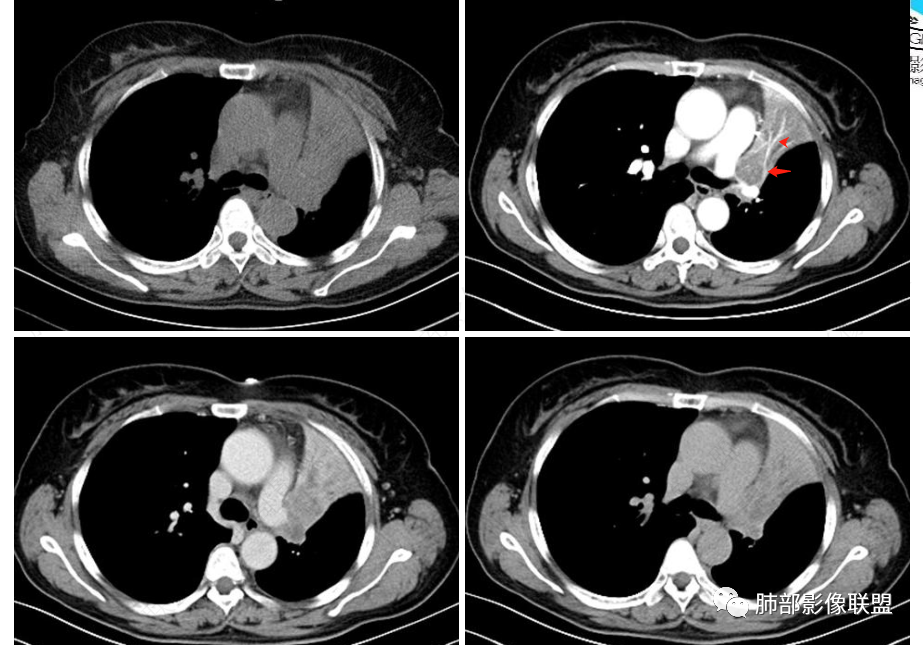

2、影像表现:正常肺背景,左肺上叶支气管腔内占位,上叶支气管截断,远端肺组织不张,强化差异衬托出肺门区结节影或块状影。增强扫描腔内占位轻中度不均匀强化,可见坏死,远端粘液栓,局部肺动脉受压、侵犯,纵膈淋巴结无明显肿大,无胸腔积液。

④小细胞肺癌属于高度恶性神经内分泌肿瘤,好发于吸烟男性,多数小细胞癌影像表现较典型,表现为肺门旁或外周边缘膨隆、边界清楚的软组织结节或肿块,由于肿瘤组织坏死不彻底,常表现为“沼泽样”坏死区,较早出现肺门和纵膈淋巴结转移,有“娘小崽大”的特点。纵隔淋巴结融合,可形成“冰冻纵膈”。小细胞癌侵袭力强,容易包埋血管形成“血管包埋征”,肿瘤沿支气管浸润时可见病灶呈鸭蹼和腊肠样凸起,相较于鳞癌而言,小细胞癌导致的阻塞性肺炎常常较轻,较少合并肺不张,少见合并胸水。

就本例而言,患者为女性,无肺气肿背景,未提及吸烟史,影像上强化程度偏轻,未见湖泊样坏死,尽管中央型肺癌中以鳞癌最多见,且造成完全阻塞及肺不张,但在女性患者诊断鳞癌仍需谨慎。支气管腔内结节,强化程度轻,涎腺肿瘤需要考虑,不典型类癌也不能除外。女性患者,未提及吸烟史,尽管未见纵膈淋巴结明显肿大,但支气管明显相关,小细胞肺癌亦应当重点排除。